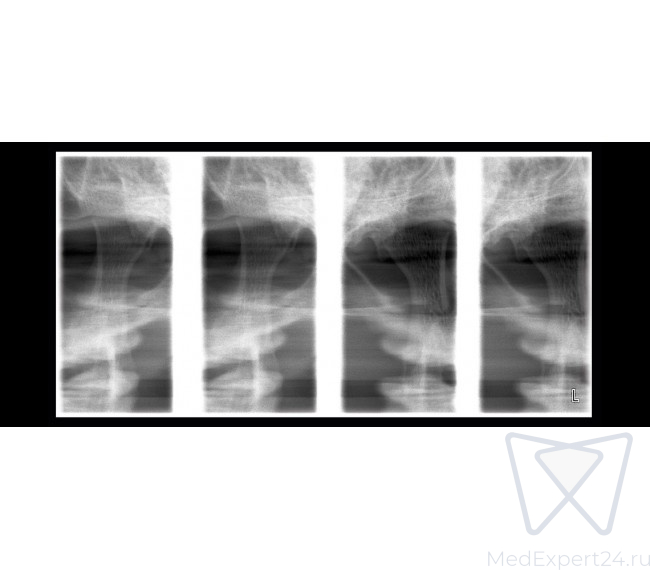

- Боковая и двойная ВНЧС программа,